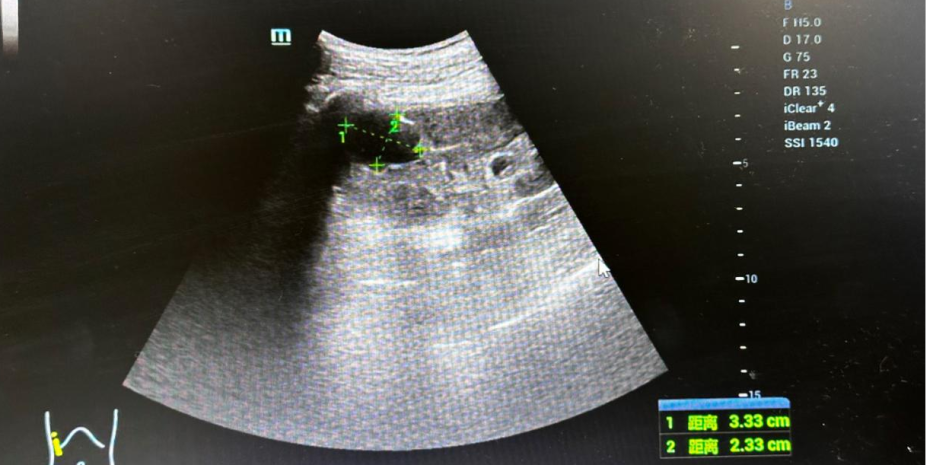

临床医师在彩超医师的配合下行肾囊肿穿刺引流,生理盐水冲洗,接着开始聚桂醇硬化治疗,屏幕显示肾囊肿逐渐缩小。

聚桂醇硬化治疗过程中彩超图片